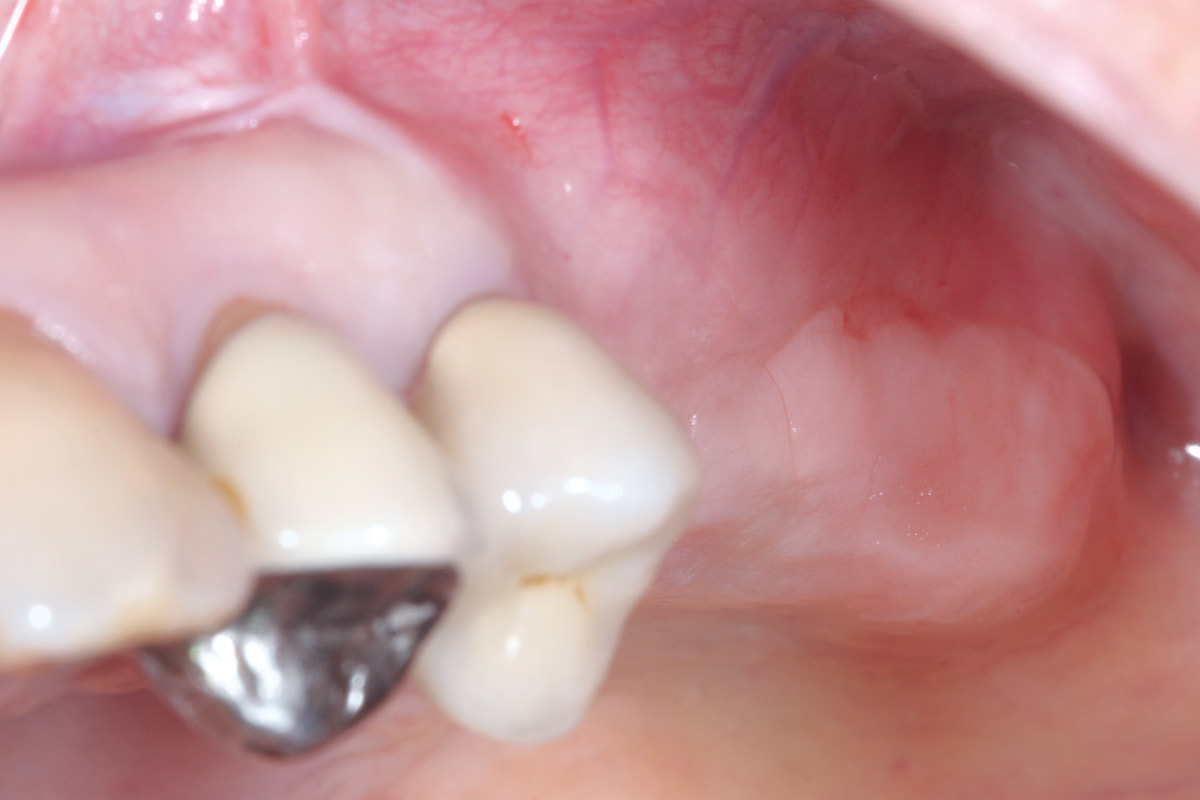

13/15 - Clinical situation 14 days after implant uncoveringTreatment of a combined horizontal and vertical bone defect in the maxilla with maxgraft® cortico in the allogenic shell technique - Dr. R. Würdinger

14/15 - Final prosthetic restoration- proper implant-crown ratio compared to the neighboring teethTreatment of a combined horizontal and vertical bone defect in the maxilla with maxgraft® cortico in the allogenic shell technique - Dr. R. Würdinger